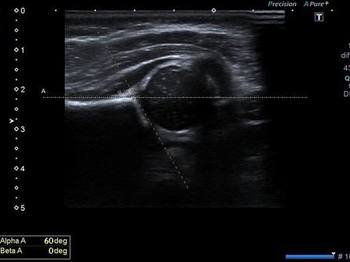

Boynumuzda ki diğer hayati organlar beynimize giden ana damarlarımızdır (Şah damarları). Ultrasononunda bu damarların açık olup olmadığı, içlerinde damar setliği bulguları ve plaklar olup olmadığı bakılır. Damar incelemesinin tam olarak yapılabilmesi için Doppler Ultrasonun da incelemeye dahil dilmesi gereklidir.